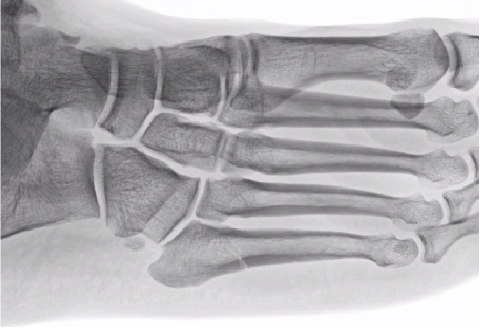

As a longtime sports fan, I have seen how Jones fractures (Figure 1) can alter the success of a season and change the careers of athletes across professional and collegiate sports. The majority do return to their sport, but some do not, with multiple surgeries, nonunions or refractures complicating the course.

It is important to recognize the age of the fracture. I have noted radiologists routinely mistaking acute fractures for stress fractures based on location. I’ve heard surgeons tell patients that their fracture isn’t healing based on a 6-week-old injury, due to signs of bone resorption, which is normal sign of healing. Unfortunately, not all Jones fractures get X-rayed the same week, let alone within a month of the injury, so they may present already showing signs of radiographic healing. Either way, I find it is common that one may overread the imaging. See Figures 2-3.